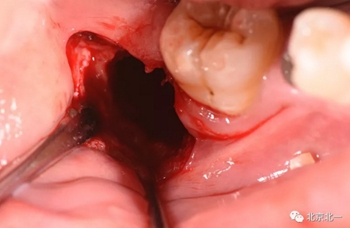

第二步:拔牙

切口設(shè)計關(guān)鍵點偏頰側(cè)。

去骨:原則暴露最大周徑線即可, 盡可能少去骨, 微創(chuàng)拔除。

截冠:有絲分裂至關(guān)重要。 保證微創(chuàng)下拔除智齒。

術(shù)后強調(diào)沖洗創(chuàng)口, 搔刮血液充盈。

縫合。

北一種植王明老師總結(jié):本病例難點在于設(shè)計多學(xué)科治療。 治療周期拉長, 患者智齒低位, 拔除困難, 容易造成神經(jīng)麻木。 必須由經(jīng)驗醫(yī)師主刀。 北一微創(chuàng)拔牙理念主張將牙齒進行有絲分裂, 進行智齒粉碎。 對工具要求較高。 較少患者痛苦。